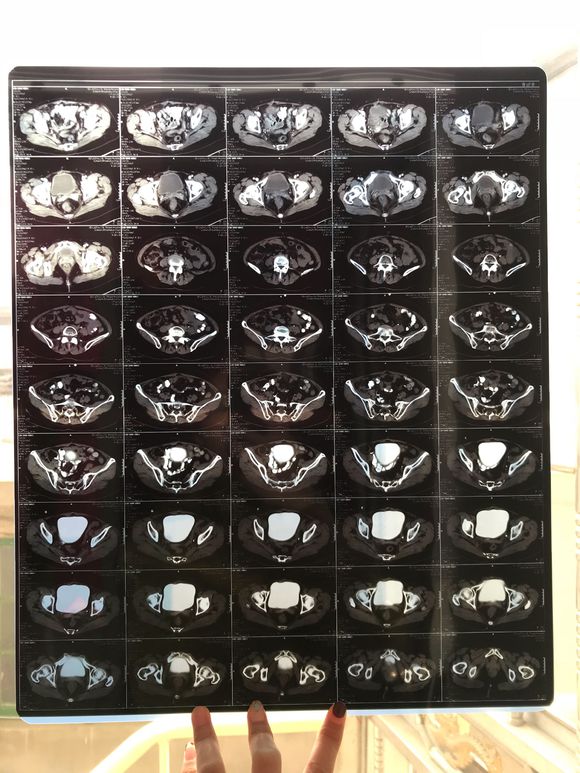

和你的故事 02019-04-09 患者家属我妈妈的病理结果报告,3期c1,大家可以帮忙看看吗,跪求了!我很急,谢谢!想知道是否严重,目前等术后出院后去肿瘤医院...